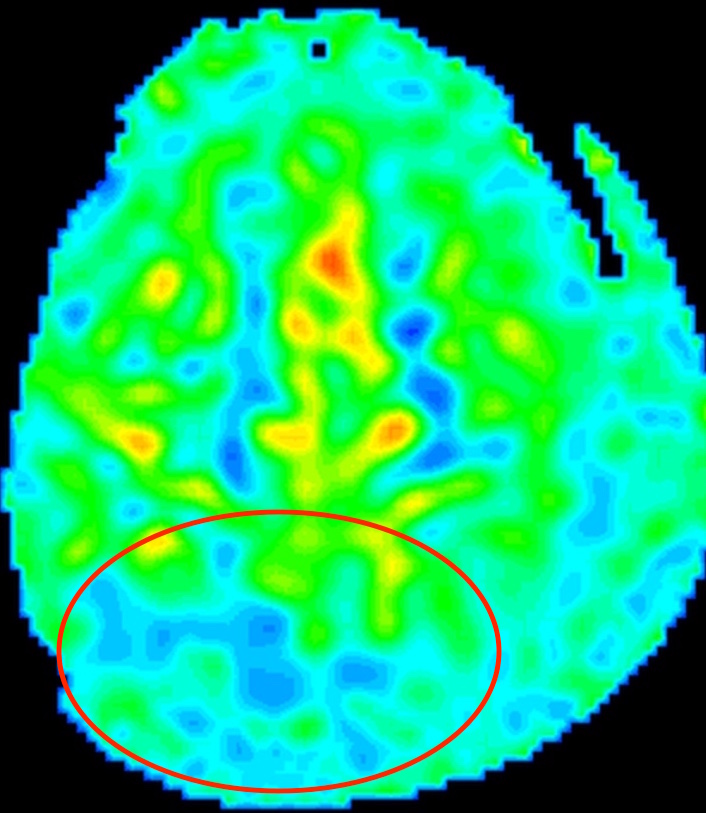

さらに、ASL(arterial spin labeling)法1)という脳血流を見る検査で、

後頭葉の血流が低下しており、これは可逆性脳血管攣縮症候群(RCVS)でしばしば見られる所見です。

このように、複数の検査方法を組み合わせる事で、この症例は椎骨動脈解離ではなく椎骨動脈に生じた可逆性脳血管攣縮症候群(RCVS)と診断できます。